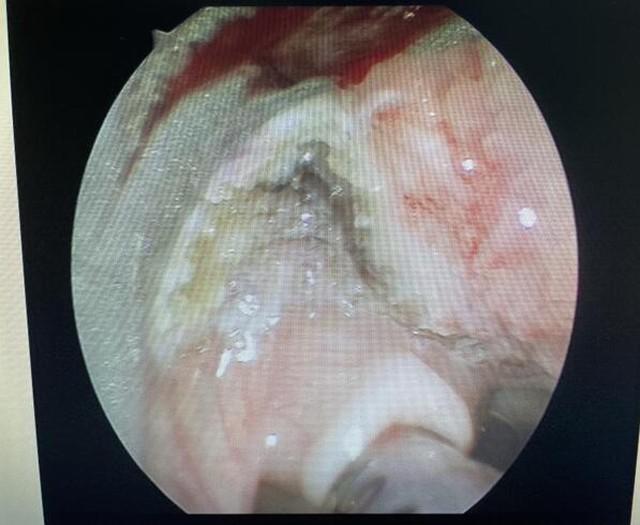

这就是插管后可见的堵在轩轩嗓子里的巨大肿物:

文章插图